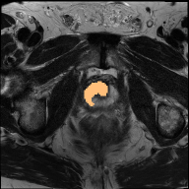

4.3 Qualitative Results of DSPIF

Some qualitative results of the proposed DSPIF are shown in Fig. 3. Both USPIF and LSPIF generate images with diverse appearances while preserving the same topological structure as the original image. Inheriting from the property of connected filters, the proposed DSPIF does not create any new contours. It is also noteworthy that monotonically increasing contrast change map pixels with the same graylevel to the same output graylevel. Differently, the output of DSPIF does not only depend on the input graylevel, but also the image structure. As shown in the first row of Fig. 3, for similar input graylevels on different pixels, USPIF may output very different graylevels on these pixels. Yet, the topological image structure is preserved.

Some qualitative segmentation results on the three datasets are shown in Fig. 4, where we can observe that the proposed DSPIF achieves accurate segmentation results.